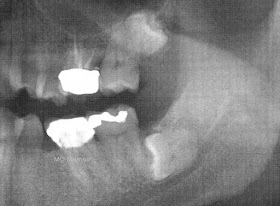

รูปที่

๑ ภาพ x-ray

ทั้งปากก่อนการผ่า ฟันคุดตัวที่เป็นปัญหาคือฟันกรามล่างขวา

(ในรูปจะอยู่ที่มุมซ้ายล่าง)

ฟันเส้นนี้ไปกดทับเส้นประสาท

(ตามแนวเส้นประสีส้ม)

ทำให้มีอาการปวดเวลาอ้าปากกว้างหรือเคี้ยวอาหาร

ฟันกรามล่างซ้าย

(ในรูปจะอยู่ที่มุมล่างขวา)

ก็เป็นแบบเดียวกัน

แต่ตอนนี้ไม่มีอาการอะไร

อีกซี่ที่เป็นระเบิดเวลาคือด้านบนซ้าย

(ในรูปจะเป็นมุมบนขวา)

ซี่นี้งอกขึ้นไปจ่อไปยังโพรงไซนัส

คั่นด้วยกระดูกบาง ๆ

ตอนนี้ยังไม่ก่อปัญหาอะไร

แต่ถ้าจำเป็นต้องถอนเมื่อไรก็เสี่ยงอยู่เหมือนกันที่จะมีการทะลุเข้าไปยังโพรงไซนัส

ก่อให้เกิดปัญหาการติดเชื้อตามมาอีก

ก่อนผ่า

คุณหมอก็ส่งไปเอ็กซ์เรย์ใหม่ทั้งปาก

ผลก็ออกมาดังรูปที่ ๑

ทำให้รู้ว่าปัญหามีมีมากกว่าที่คิด

คือมีฟันคุดทั้งหมด ๓ ซี่

สองซี่อยู่ที่กรามล่างซ้ายและขวา

อีกซี่หนึ่งอยู่ที่กรามซ้ายบน